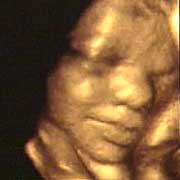

圖文:胎兒子宮內(nèi)表情豐富 專家稱提供研究新依據(jù)

中新網(wǎng)9月13日電 英國天空新聞報(bào)道,英國科學(xué)家圖亞特·坎貝爾最近利用先進(jìn)的掃描技術(shù)清晰地拍下了孕婦子宮中胎兒的表情,透過他拍攝的照片,人們可以清楚的看到一個(gè)尚未降臨世間的小生命喜、怒、哀、樂的表情。

斯圖亞特.坎貝爾是倫敦著名的產(chǎn)科教授,他利用超聲掃描技術(shù)拍攝到了胎兒在子宮中打呵欠、眨眼、吮手指、哭泣甚至微笑的畫面,這些都為胎兒行為的研究提供了新的依據(jù),專家認(rèn)為,這一突破將推動(dòng)?jì)雰航】悼茖W(xué)的發(fā)展,包括對(duì)唐氏綜合癥等嬰幼兒疾病的診治將起到極大的推動(dòng)作用。